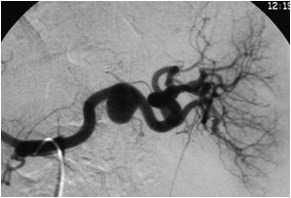

脾动脉瘤栓塞技术的基本要点 栓塞前最重要的是CTA的检查,以利于脾动脉瘤的治疗计划的制定。CTA可以发现脾动脉瘤载瘤动脉的大小和走行(和导管的选择相关),脾动脉瘤的位置和大小,脾动脉瘤的类型(和选择栓塞方式相关)以及脾动脉瘤伴发病症的。术前必备6~8F的弯曲的引导导管,主要用于稳定工作导管,为释放各种栓塞器械或栓塞剂做准备。同时需要准备Cobra 或 各种适形弯曲导管作为工作导管,其经过引导导管进入载瘤动脉。各种亲水导丝,超长和超硬亲水导丝,以备一旦需要置换各种需要的工作的导管。微导管主要用于困难的病例。事实上,在大多数情况下微导管的应用使原本困难的病例变得容易。围手术期广谱抗菌素的应用。作为血管内的异物,栓塞部位一旦发生感染后果非常严重。 弹簧栓子栓塞技术(Coil embolization) Trapping 技术:又称为sandwich技术(三明治技术)和backdoor-frontdoor技术(前后门技术)。是最为常用的脾动脉瘤栓塞技术。在微导管技术的支持下最适合超选择末梢动脉瘤的栓塞,宽颈和大动脉瘤的栓塞治疗。主要缺点是可以造成脾和部分脾梗死,但一旦栓塞技术成功,再通的机会罕见

脾动脉瘤栓塞Trapping 技术

脾动脉Trapping/packing技术

脾动脉瘤 Trapping/packing